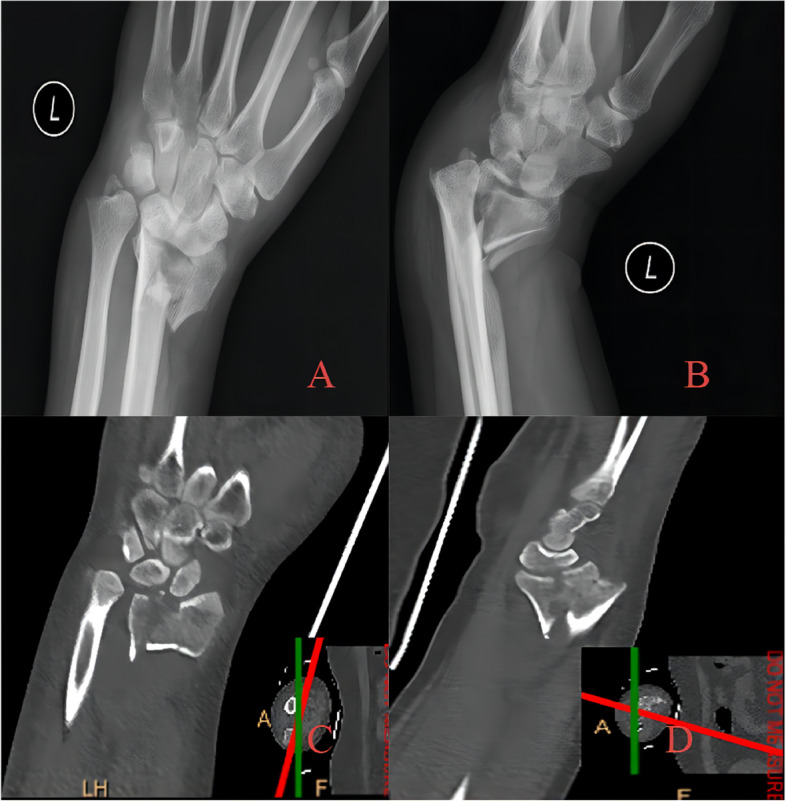

Fig. 4.

A 27-year-old patient with die-punch DRF. Radiographic examination showed that the lunate surface of the wrist joint was split longitudinally and collapsed downwards, and the fracture fragment was displaced to the palmar side. A AP radiography showed that the epiphysis and articular surface were involved; B Lateral radiography showed fracture; C Axial view of the articular surface of the radius. Fracture involving articular surface of intermediate column and lateral column are noticed; D Coronal plane, collapse of the lunate articular surface is obvious; E Sagittal plane, bone fragment shifted to dorsal side F Three-dimensional reconstruction of CT image